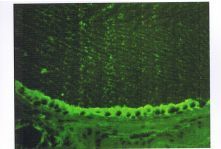

过去用于检测Tg自身抗体的方法有:沉淀试验、间接免疫荧光(11F)、血凝试验、ELISA和放射定量分析。目前常用IIF法和ELISA法。IIF法荧光图形为在甲状腺滤泡腔内出现波浪状着染。 本文来自实验室前沿